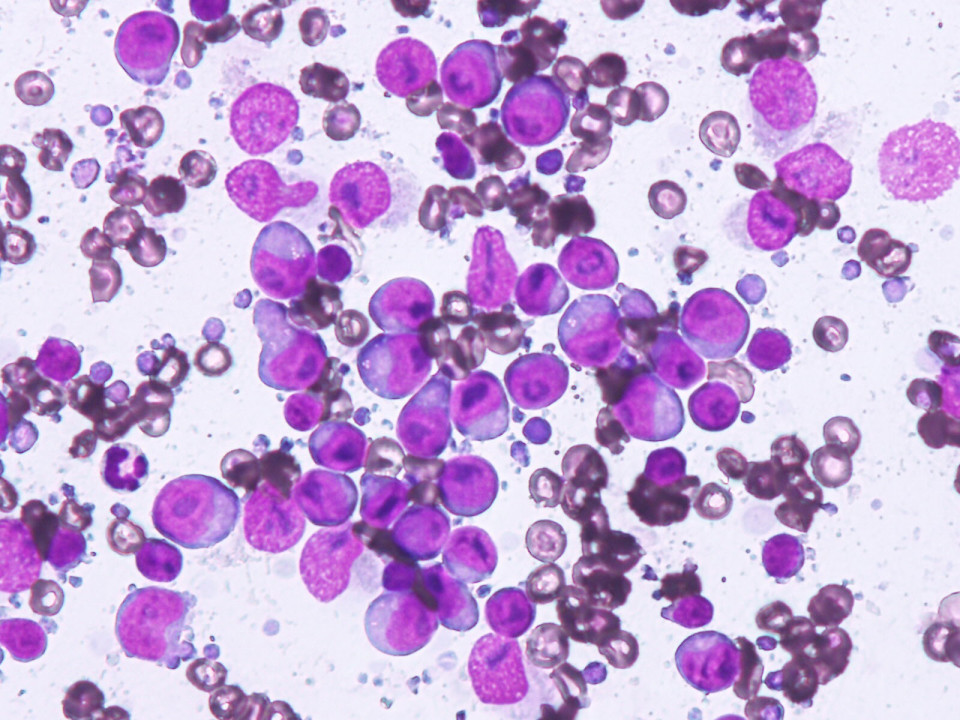

身体中にあるリンパ球ががん化する病気のリンパ腫。ヒトでは悪性リンパ腫と言われます。わんちゃん、ねこちゃんでは最も多い腫瘍の中の一つです。わんちゃんでは体の表層のリンパ腺が腫れる多中心型リンパ腫が最も多く、最近では胃腸にできる消化器型リンパ腫や皮膚・粘膜にできやすい皮膚型リンパ腫も増えているようです。ねこちゃんでは胃腸にできる消化器型リンパ腫にかかる場合が多く、他にも鼻にできる鼻腔型や胸の中にできる縦隔型などもあります。

リンパ腫のタイプによって治療法は異なりますが、抗がん剤を使った化学療法や局所的なものには放射線療法、抗がん剤と併用して免疫療法も行われます。

猫の消化器型高分化型リンパ腫。

高齢のねこちゃんで多い胃腸のリンパ腫。特にこの高分化型リンパ腫ではお薬の治療で長期にがんを抑えて普通の生活を送れることが多いです。

case.1

雑種猫、9歳齢、不妊雌。慢性の下痢、体重減少。組織生検にて高分化型リンパ腫の診断。

chlorambucil、predonisoneの内服治療。

症状消失、長期寛解生存。

case.2

case.1

結腸から直腸に発生した未分化型リンパ腫。

ミニチュアダックスフント、8歳齢、避妊雌。

肛門からの脱腸を繰り返し、結腸粘膜の組織生検で未分化型リンパ腫と診断。

L-CHOP療法を中心とした多剤併用化学療法を実施。寛解するも早期再燃し、ACNU、CCNU、DTICでサルベージ療法を実施。

結腸に発生した犬の高分化型リンパ腫。

雑種犬、9歳齢、避妊雌。組織生検による病理組織診断により高分化型リンパ腫と診断。

melphalan 0.05mg/kg sid-eod、predonisolone 0.5-1.5mg/kg sid 内服による治療で寛解。